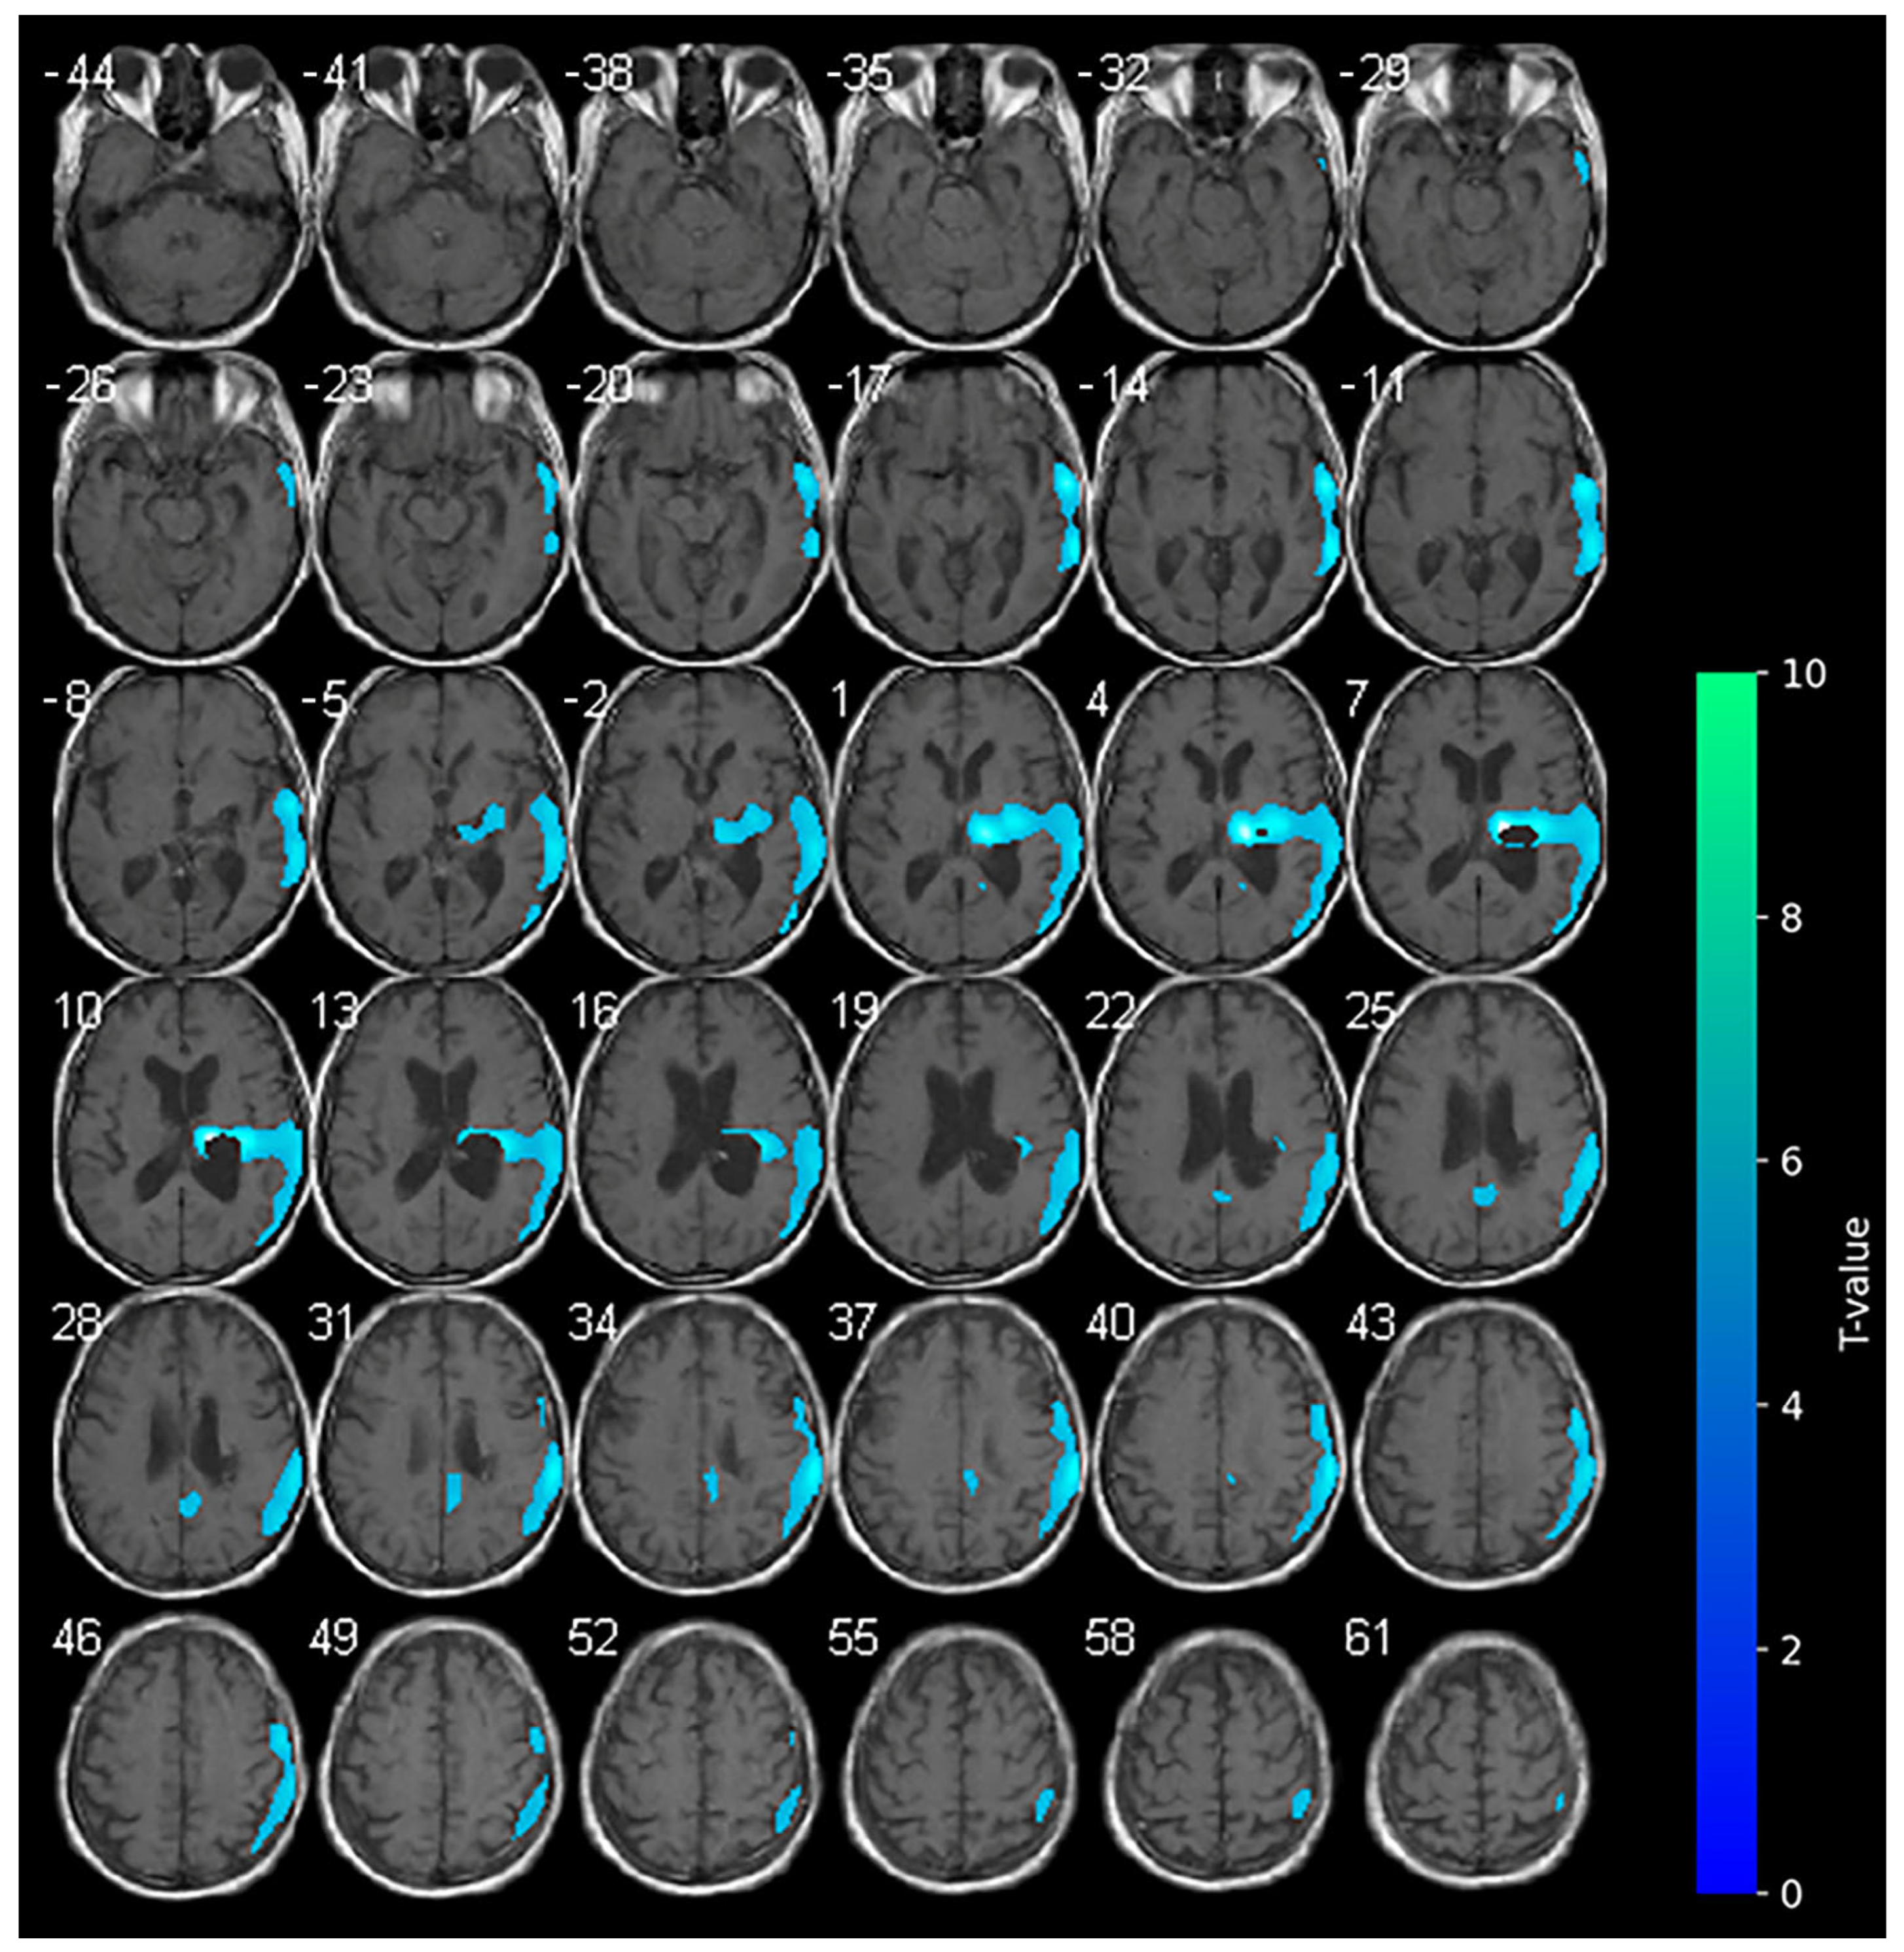

3.3. 18F-FDG-PET and Cathodal-tDCS (T2)

No variations in the marked hypometabolism were detected in the right hemorrhagic nucleo-capsular lesion. The right fronto-parietal cortex showed reduced metabolism, a condition which was not previously observed at the baseline. No areas of significantly increased metabolism were appreciable during cathodal-tDCS (Figure 3).

A clinical improvement was observed at T2. The NIHSS score decreased to 16 and the mRS improved to 4, suggesting a partial recovery of function and reduced dependency in some basic activities of daily living. Of note, motor function showed early indications of recovery, as evidenced by an increase in the MI scores to 9 for the upper limb and 18 for the lower limb. The LCF demonstrated stability at level 6, even though the responses to requested commands were consistently more suitable.

With regard to cathodal-tDCS administered on the unaffected side, brain metabolism appeared reduced in the ipsilateral hemisphere, as expected. In the occipital and frontal regions of the affected side, we observed hypoactivation that was not present at the baseline. The expected reduction in metabolism during cathodal stimulation may indicate a suppression of maladaptive hyperactivity in the local stimulated area, also resulting in a more balanced interhemispheric interaction. In addition, the PET images may reflect the patient’s progressive clinical improvements, including reductions in NIHSS and mRS scores and modest gains in motor function, particularly in the lower limb. Furthermore, the observed progressive improvement in cognitive performance may be linked to enhanced network integration with a more efficient brain network reconfiguration (cortical-subcortical) [34].

Figure 3. SPM analysis results (t-maps) at T2. The blue areas indicate voxel values of the patient that were significantly hypometabolic from the normal control group (p > 0.001).